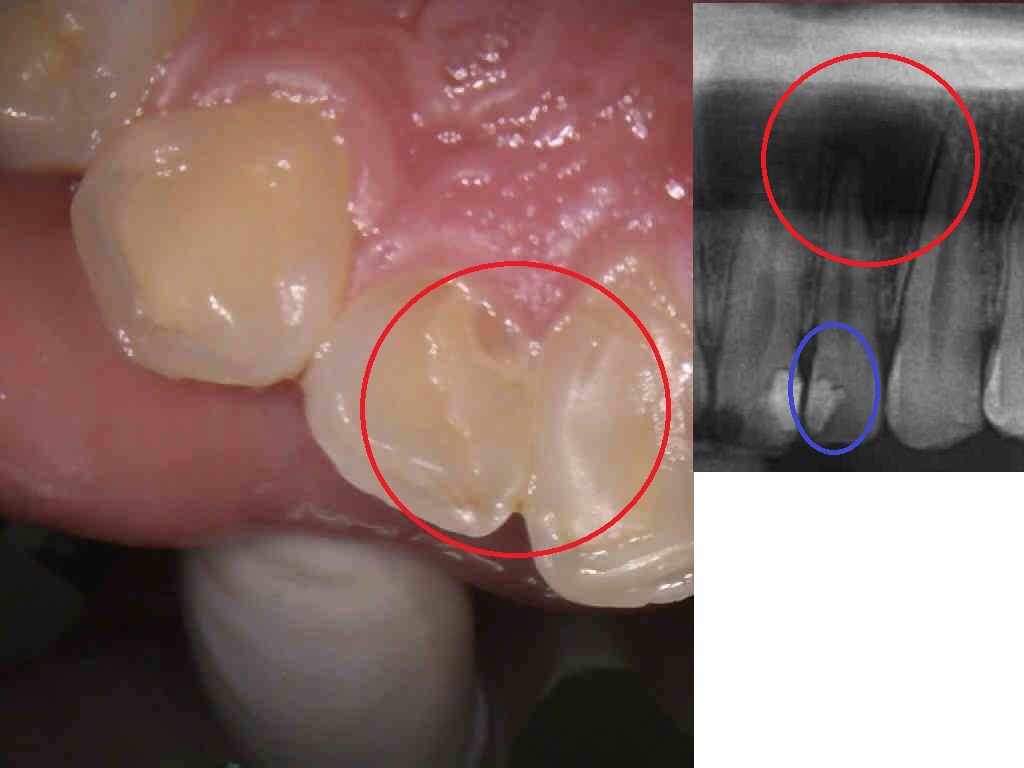

無理に残した神経

左写真赤丸は、他院治療の詰め物。

右写真赤丸は、直径20MM以上の膿の病巣。

他店で抜歯宣告。激痛、かなり腫れた状態でセカンドオピニオンで来院。

右写真青丸は、神経内まで削って感染させた状態でそのまま詰めた物が原因。

先端まで確実に、感染した神経をマイクロ、マイクロエキスカを使用し完全に除去。

大きな病巣も完全に改善し、根の先端まで隙間なく詰め完了。